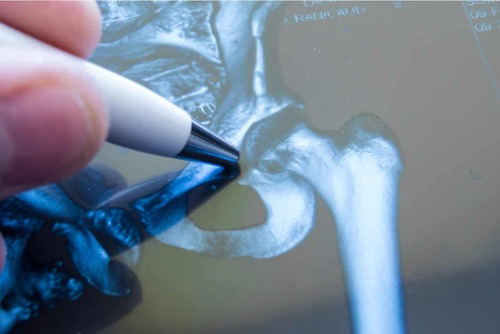

Di solito sono necessari anche alcuni esami complementari per escludere altre lesioni. Uno dei più utilizzati è la radiografia, attraverso la quale è possibile osservare la presenza di frattura o anomalia ossea.

La radiografia è particolarmente utile se c’è stato un trauma. Tuttavia, con i raggi X i tessuti molli non sono visibili, per cui a volte si ricorre alla risonanza magnetica.